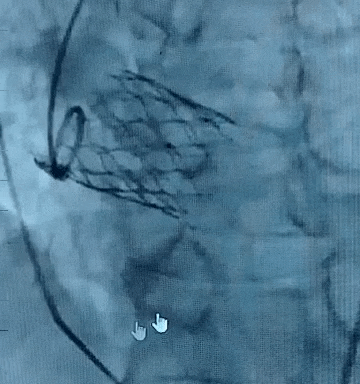

武汉大学人民医院黄兵教授结合病例分享了ScienCrown自膨短瓣在单纯主动脉瓣反流(PAR)中的应用价值。CASE 1为主动脉瓣退行性变并重度PAR,术前CT示瓣环直径23.7mm,敞口流出道,无多平面锚定,STJ及升主可见明显扩张,属于TYPE 4型反流患者(指LVOT、瓣环和升主动脉均不能锚定的患者)。术中应用该款自膨短瓣出色完成窦部增宽单一瓣环平面锚定,锚定平面稳定,且区别于传统自膨瓣应用于PAR的“大oversize理论”,术中小oversize选择TAVTF 27mm瓣膜,进一步减少反流患者传导阻滞风险。最终造影示瓣膜位置与形态良好,无瓣周漏。

CASE 1:脱钩后造影